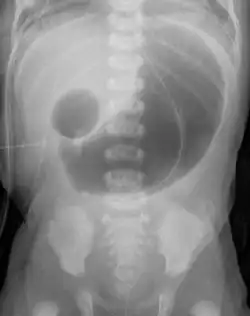

| Radiograph with double bubble sign indicating duodenal atresia | |

If not diagnosed in utero, infants with intestinal atresia are typically diagnosed at day 1 or day 2 after presenting with eating problems, vomiting, and/or failure to have a bowel movement.[3] Diagnosis can be confirmed with an X-ray, and typically followed with an upper gastrointestinal series, lower gastrointestinal series, and ultrasound.[5][3]

- Duodenal atresia – malformation of the duodenum, part of the intestine that empties from the stomach, and first section of the small intestine